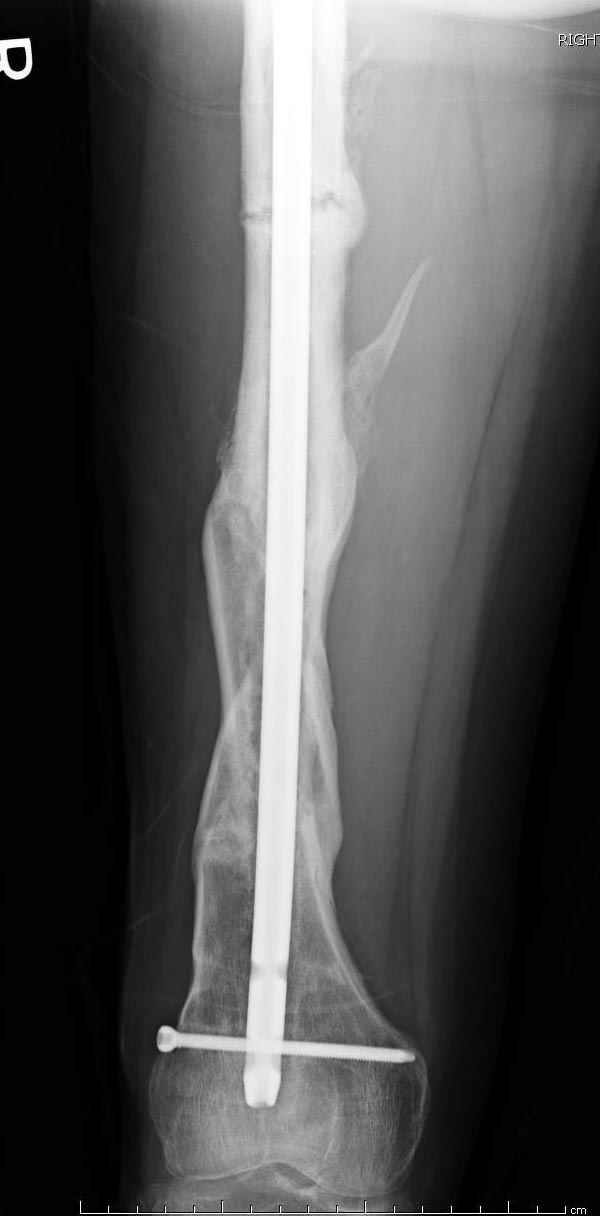

Инфекция канала и стрессовый перелом:

Представляю снимки больного с политравмой: леченного в другом мед.учреждении по поводу открытого перелома бедра, сперва аппаратом наружной фиксации, затем пластиной. Обратился к нам через 8 месяцев после удаления пластины с проблемой несросщего перелома бедренной кости, без клинических проявлении к инфицированию (не все снимки сохранены)

Рутинный интрамедуллярный остеосинтез с расверливанием и с фиксацией реконструктивным трокантерик штифтом (рис №1, №2),

если первые 4 месяца послеоперационного периода проходил без проблем, но на 5 месяце появились боли в дистальном отделе бедра и температура, т.е. симптомы медуллярного инфицирования (рис №3, №4).

Замена реконструктивного штифта “Custom made Nail” с антибиотиком (рис №5, №6),

после промывки канала с рассверливанием внутреннего кортекса, через 4 недели антибиотический штифт удалили, оспалителный процесс остановлен и бедро сросся.

Мы не дождались “Happy End”, у больного IQ в пределах 70%, через 6 месяцев вернулся после небольшой травмы, споткнувшись получил перелом

того же бедра (рис №7).

На следующий день произвели интрамедуллярный остеосинтез: этапы во время операции (рис №8, №9)

и последующих снимках (рис №10, 11, 12, 13) перелом сростается и передвигается с полной нагрузкой.

При обзоре причин перелома, на снимке №2 обнаружили, что один из стержней аппарата наружной фиксации проходил только через передний кортекальный слой, что создало стрессовую зону на бедре и в результате перелом из-за незначительной травмы.